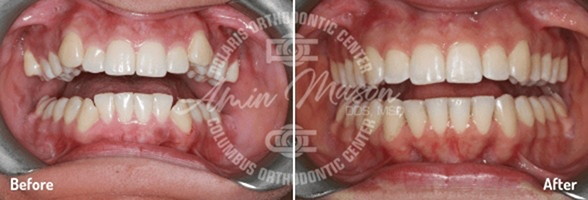

Case 6

A 23-year-old female patient presented to our office with severe crowding and worn teeth. The patient was not happy with the appearance of the teeth and the shape of the restoration on tooth #9. The patient was treated with extraction of 4 premolar teeth and the Damon system in 20 months. She will undergo whitening and restoration of tooth #9 for improved aesthetics.